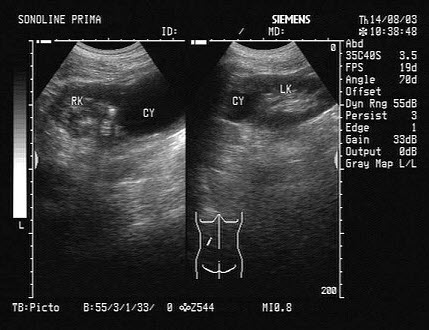

D.睾丸扭转

根据超声图像所示,该病例为哪型肾积水()

A.菱角型

B.烟斗型

C.花朵型

D.调色板型

E.巨大囊肿型